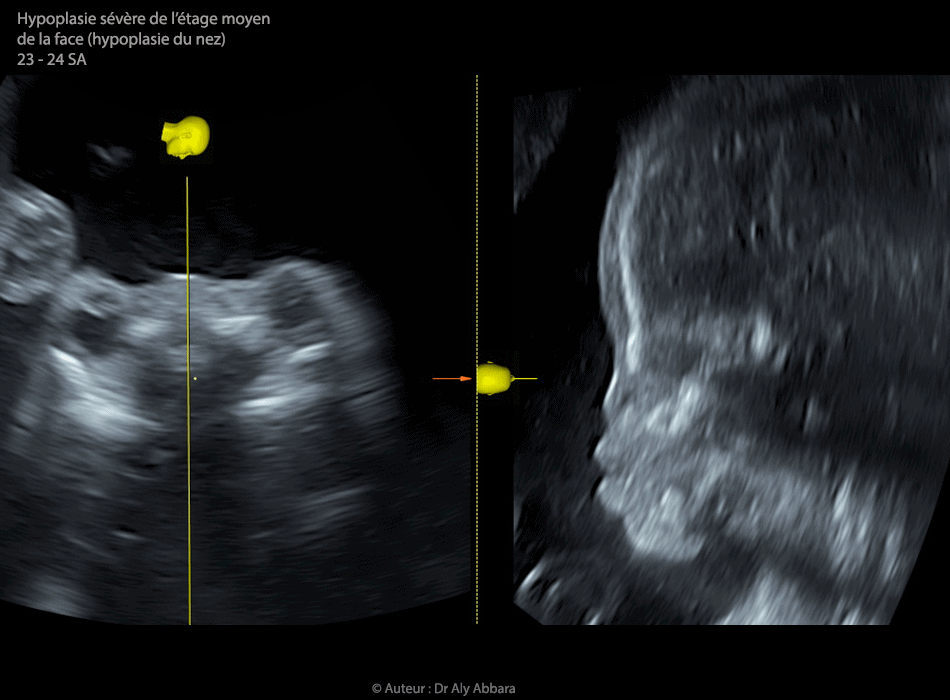

• Vidéo et images échographiques à 23 et 24 SA montrant une sévère hypoplasie de l'étage moyen de la face (faciès ou phénotype de Binder) se manifestant par l'hypoplasie sévère nez :

• pyramide nasale rudimentaire ;

• os propre de nez présent, mais en position verticale ;

• effondrement de la racine du nez ;

• narines non identifiables ;

• maxillaire supérieur en retrait vers l'arrière avec élargissement de son angle d'ouverture arrière ;

• l'angle : maxillaire > os propre du nez > mandibule (angle MNM) mesure 6° degrés (normal = 13,5° entre 16 et 36 SA IC = 13,3-13,8 et limites 9-19,6°) ;

• voûte du palais est sans particularité ;

• hypertélorisme et exophtalmie ;

• suture crâniennes sans particularité ;

• la déglutition et le flux au niveau de choanes sont bien observés ;

• Il s'agit d'une malformation isolée, avec caryotype fœtal normal.

• Biométrie fœtale est au 28e percentile.

• Aucune prise de médicaments ou de substances toxiques en pré et per conception.

• Avis de l'expertise en stomatologie anténatale : sont à  craindre les difficultés à  la respiration spontanée à  la naissance avec la nécessité d’assistance respiratoire par (trachéotomie, intubation...) ; la chirurgie réparatrice est difficile et ne pouvant pas être réalisée en période néonatale précoce.

• Évolution : sévère menace d'accouchement prématuré à 29 SA provoquée par le développement entre 24 et 29 SA d'un hydramnios sévère nécessitant une amnio-drainage de deux litres de liquide amniotique suivie d'une interruption médicale de grossesse.